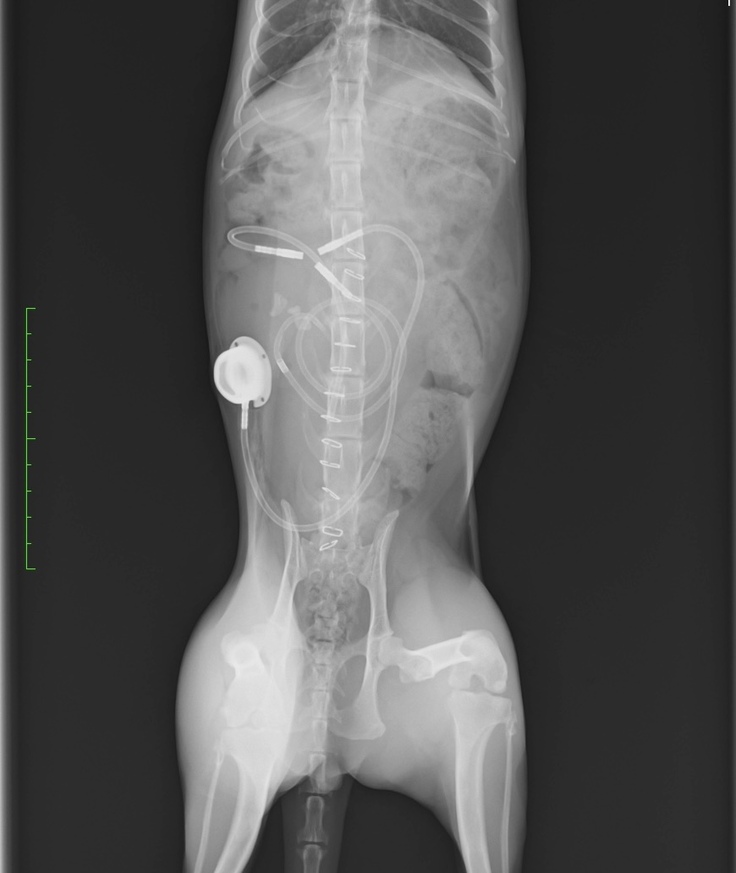

手術後のお腹の中はどうなっているのかな?と

気になったので写真を頂いてみました!

医療技術の進歩は凄いですね‼️

今後はSUBシステムのポート洗浄を

行う必要があります!